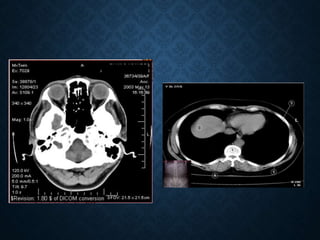

TOMOGRAFIA COMPUTADORIZADA

• A Tomografia Computadorizada é

um método de diagnóstico por

imagem que utiliza radiação

ionizante na formação de imagens

do corpo humano em cortes

seccionados .

TOMOGRAFIA COMPUTADORIZADA • ATomografia Computadorizada é um método de diagnóstico por imagem que utiliza radiação ionizante na formação de imagens do corpo humano em cortes seccionados .